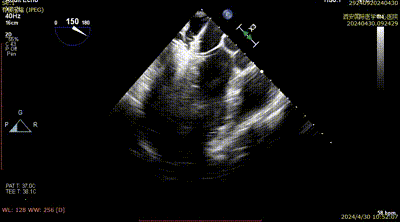

患者为69岁男性,因胸闷气短一周入院。心脏彩超提示:前叶长度:2.5cm,后叶长度:1.6cm,瓣口面积:6.0cm²,病变宽度:13mm。

经心脏瓣膜介入团队评估后,决定先于2区植入一枚二尖瓣夹,后根据反流情况,考虑是否植入第二枚夹子。在DragonFly™精准操作下,最终患者术后反流降至1+,跨瓣压差为2mmHg,肺静脉逆流消失。

Case 1影像资料

术后二尖瓣反流评估

术后结果